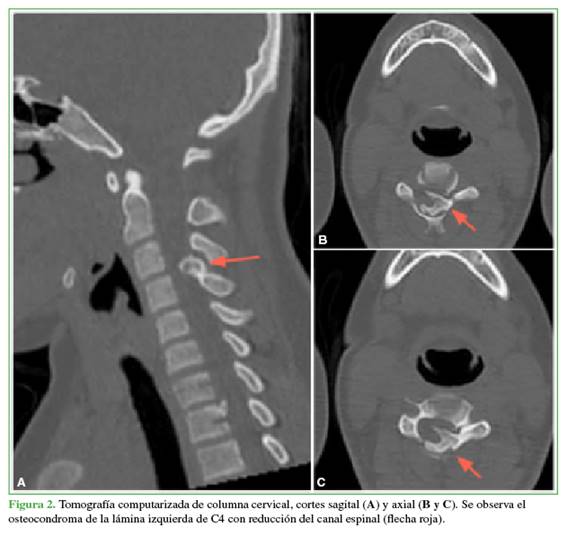

La paciente no tuvo complicaciones neurológicas y fue dada de alta al tercer día de la cirugía. Se mantuvo la inmovilización con un collar rígido durante 2 meses. El examen patológico confirmó el diagnóstico de osteocondroma. Tres meses después de la cirugía, desarrolló una cifosis local en el segmento C4-C5 que actualmente está en observación. A los 2 años de la intervención, no hay evidencia de recurrencia local en las imágenes de TC y RM (Figura 5).

Tanto el osteocondroma pediculado de T1 como el hallazgo en el proceso espinoso de C2 no habían cambiado con respecto a las imágenes previas, por lo que se optó por un tratamiento conservador a la fecha.

En la actualidad, la paciente no sufre dolor y participa activamente en deportes.